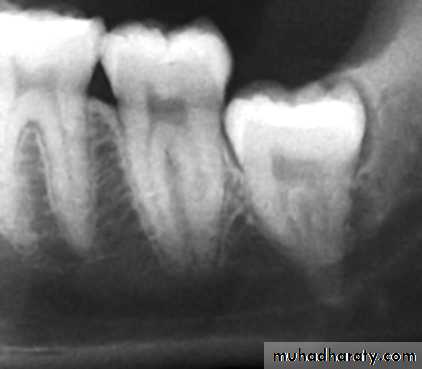

Dental floss abrasion. Note the obliteration of the pulp chambers and reduction in size of the root canals.